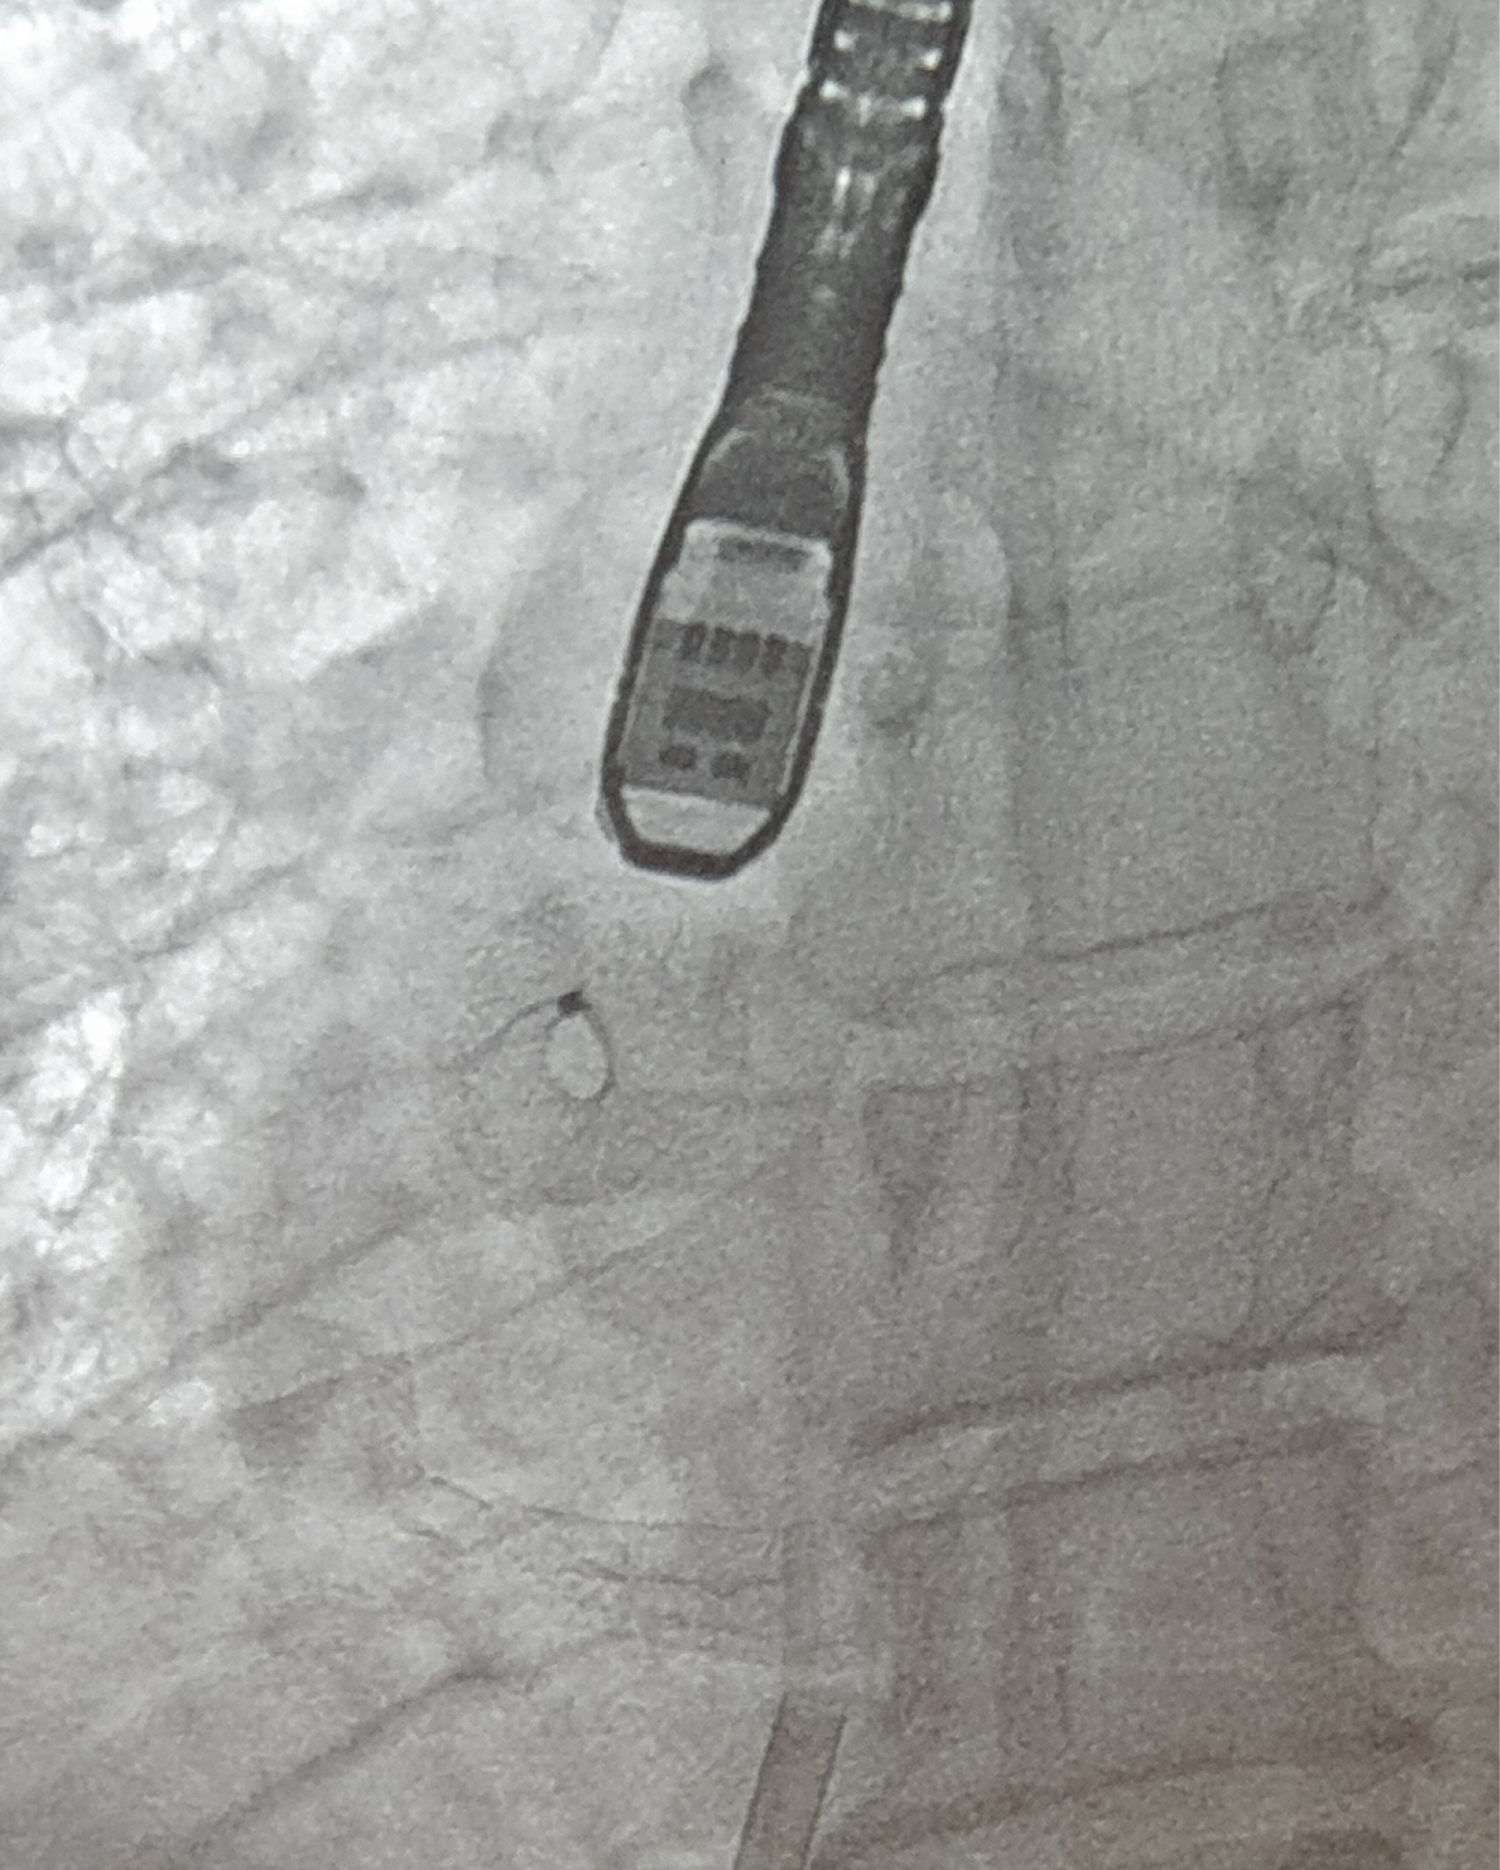

A 55-year-old man, hypertensive with type 2 insulin-dependent diabetes mellitus, dyslipidaemia and obesity (BMI: 33.96 kg/m2) underwent clinical evaluation because of more-than-3-month effort dyspnoea (NYHA III). His past medical history consisted of prior anterior ST-elevation myocardial infarction (STEMI) treated by percutaneous coronary intervention (PCI) with drug-eluting stent (DES) implantation on the left descending artery (LDA) and on the posterolateral artery (PLA). At follow-up, both DES resulted occluded while another PCI with DES implantation was performed on the obtuse marginal artery (OM1) due to a symptomatic critical CAD. A subsequent stress cardiac magnetic resonance (CMR) showed a moderate LV dysfunction (LVEF 40%) without viability of the left ventricular apex and the anterior wall. The patient was on optimal medical therapy including beta-blockers, ARNI, SGLT-2 inhibitor, diuretic, mineralocorticoid receptor antagonist). According to the recent 2021 ESC Guidelines on HF, the patient was diagnosed with advanced heart failure [1]: he presented typical symptoms of HF with persisting high N-terminal prohormone of Brain Natriuretic Peptide (NT-proBNP) and evident cardiac structural abnormalities; moreover, he had 4 episodes of pulmonary congestion requiring hospitalization, the last registered 6 months before, and developed a severe inability even to low-grade exercise. Due to this clinical scenario, the patient was admitted to our Cardiology Unit. Baseline trans-thoracic echocardiography confirmed left ventricle systolic impairment (LVEF 40%), but showed no right heart dysfunction nor severe pulmonary hypertension (e.g. pulmonary artery systolic pressure - PASP - ≥ 60 mmHg). Estimated ultrasonographic LAP at rest was 26 mmHg. Coronary angiography confirmed an occlusive in-stent restenosis on the LAD and a critical stenosis in the right coronary artery treated by DES implantation. Right heart catheterization reported mild pulmonary hypertension (PASP: 32 mmHg, diastolic pulmonary artery pressure - PAP: 24 mmHg, mean PAP: 27 mmHg) and increased PCWP at rest which was 20 mmHg. Based on these data the patient was considered a candidate for IAST using an 8-mm-diameter Atrial Flow Regulator device (Occlutech™). The procedure was successfully performed under general anaesthesia, through a hybrid fluoroscopic and transoesophageal echocardiographic guide. Procedural steps are described by Paitazoglou C, et al. [12] and are summarized in Figure 1. No complications were reported and the LAP has been acutely reduced following the generation of an iatrogenic inter-atrial shunt (final Qp/Qs 1.2) (Figure 2 and Figure 3). Patient was discharged 2 days after the procedures on dual antiplatelet therapy in association with beta-blocker, ARNI, diuretic, mineralocorticoid receptor antagonist, SGLT-2 inhibitor.

Figure 3: Zoomed 3D-Echocardiographic view of atrial flow regulator. View Figure 3